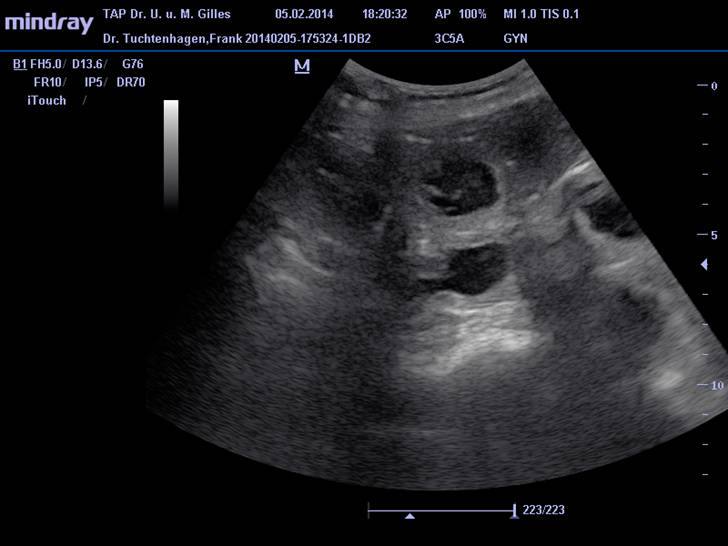

Ultraschall läßt 9 Welpen erwarten!

Endlich ist es soweit, wir haben Gewissheit: unsere Labelle ist tragend.

In der Ultraschalluntersuchung vom 5.2.2014 lassen sich die Anlagen von 9 Welpen erkennen.

Alle, soweit so früh schon beurteilbar, normal weit entwickelt.

Nächste Woche gibt's dann nochmal neue aktuelle Ultraschallbilder.